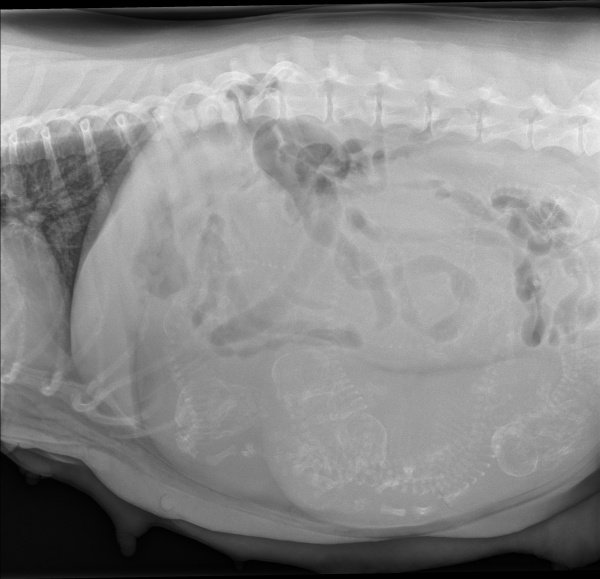

Lizzy re-presented after the unsuccessful attempt to birth at home. Ultrasound examination showed signs of fetal distress. Fetal heart rates decreased to 130-150 bpm. Radiographs showed 8-10 puppies still present in the uterus indicating a much higher risk for Lizzy and the puppies.